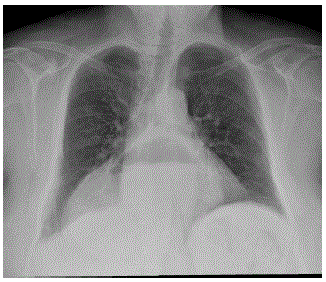

Mulher de 60 anos de idade refere dor epigástrica, tosse e náuseas após as refeições há cerca de 1 ano. Realizou uma radiografia de tórax com a imagem abaixo:

Qual é o diagnóstico mais provável?